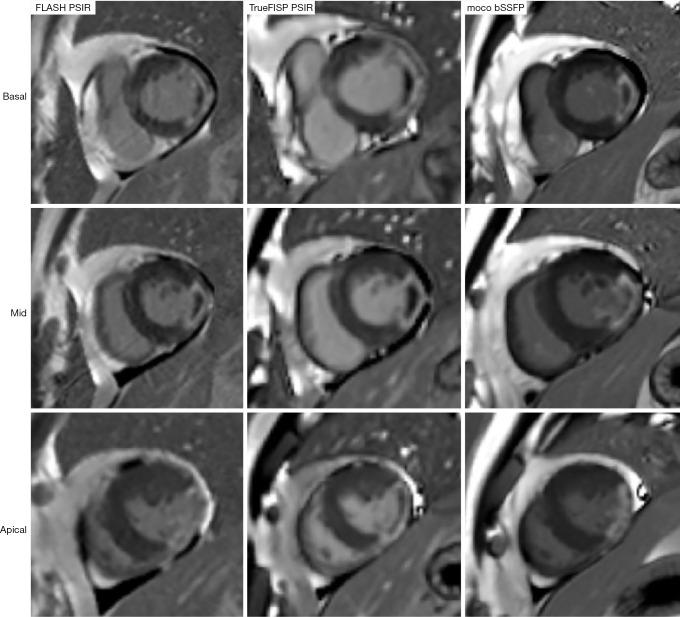

Segmented phase-sensitive inversion recovery (PSIR) turbo fast low-angle shot (FLASH) has become the reference standard sequence for late gadolinium enhancement (LGE) cardiac magnetic resonance (CMR) imaging. However, it has a long scanning time, requires multiple breath holds, and is prone to motion artifacts. This study aimed to compare the accuracy of two fast LGE sequences with FLASH PSIR in acute myocardial infarction (AMI) detection and quantification of LGE.

A total of 110 AMI patients (90 males, 58.61±10.9 years) were included in our analyses. Of these, 100 patients (84 males, 58.6±10.9 years) presented LGE (+), and 60 patients developed MVO. Participants were divided into three groups according to the LGE results, namely LGE (-), LGE (+) without MVO, and LGE (+) with MVO. The overall IQ score and CNR for the two fast sequences [single-shot true fast imaging with steady-state precession (TrueFISP PSIR), PSIR motion-corrected, free-breathing single-shot balanced steady-state free precession (moco bSSFP)] were significantly higher than those for the FLASH PSIR (P<0.001). On visual assessment, the number of layers (P=0.20 and 0.22, respectively) and segments (P=0.09 and 0.32, respectively) for LGE displayed no difference and showed excellent matching with those of FLASH PSIR. There were no significant differences in LGE mass (P=0.61 and 0.83, respectively) and MVO mass (P=0.15 and 0.55, respectively) between the FLASH PSIR and the two fast sequences.

分段相敏反转恢复(PSIR)快速低角度激发(FLASH)已成为延迟钆增强(LGE)心脏磁共振(CMR)成像的参考标准序列。然而,其扫描时间长,需要多次屏气,且容易出现运动伪影。本研究旨在比较两种快速LGE序列与FLASH PSIR在急性心肌梗死(AMI)检测及LGE定量方面的准确性。

共有110例AMI患者(90例男性,年龄58.61±10.9岁)纳入分析。其中,100例患者(84例男性,年龄58.6±10.9岁)出现LGE(+),60例患者发生MVO。根据LGE结果将参与者分为三组,即LGE(-)组、无MVO的LGE(+)组和有MVO的LGE(+)组。两种快速序列[单次激发稳态进动真快速成像(TrueFISP PSIR)、PSIR运动校正自由呼吸单次激发平衡稳态自由进动(moco bSSFP)]的整体IQ评分和CNR均显著高于FLASH PSIR(P<0.001)。视觉评估显示,LGE的层数(分别为P=0.20和0.22)和节段数(分别为P=0.09和0.32)无差异,且与FLASH PSIR的层数和节段数匹配良好。FLASH PSIR与两种快速序列在LGE质量(分别为P=0.61和0.83)和MVO质量(分别为P=0.15和0.55)方面无显著差异。